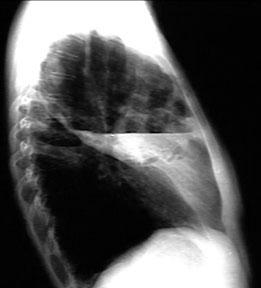

胸部X线检查可诊断和区分肺炎,肺脓肿和脓胸。肺脓肿和肺炎需要药物治疗,而脓胸经常需手术治疗。胸部X线片如下所示。

在胸部X线片,发现脓胸而不是肺脓肿的气液平面向胸壁延伸,气液平面跨过肺裂延伸,并逐渐变细。

胸部X线片上应仔细检查肋膈角,以评估预示积液或脓胸的液体是否出现。

患者侧位胸部X线片显示胸膜液是否可移动并分层或是否限于局部。